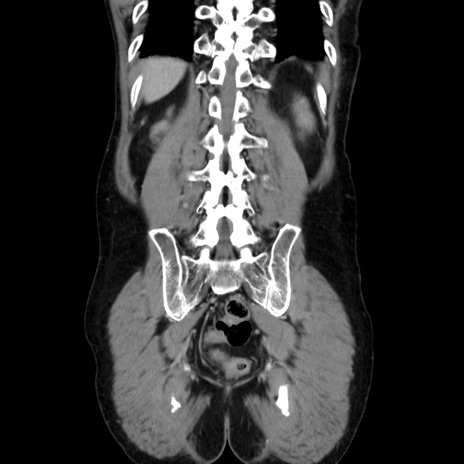

症例37(冠状断像)

【症例】40歳代 男性

【主訴】腹痛

【現病歴】4時間ほど前に電車に乗車中に臍部上より腹痛出現。徐々に増悪し起立困難となり、救急外来受診。生ものは数日食べていない。今朝お雑煮を食べた。

【身体所見】BT 36.8℃、BP 117/84mmHg、HR 91/min、SpO2 97%、苦悶様、腹部:臍上部広範囲圧痛あり、反跳痛±

【データ】WBC 8100、CRP 0.03